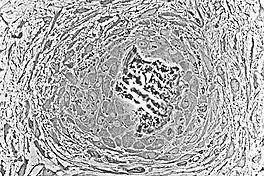

Major features of the bone-forming complex, the osteon, composed of osteoblasts and osteocytes.